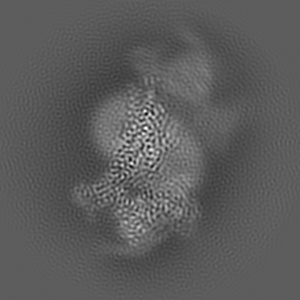

SR17018-bound mu-opioid receptor-Gi complex

Single-particle3.2 Å

Sample: fentanyl bound mu-opioid receptor-G protein complex

Molecular recognition of morphine and fentanyl by the human mu-opioid receptor.

(2022) Cell , 185 , 4361 - 4375.e19